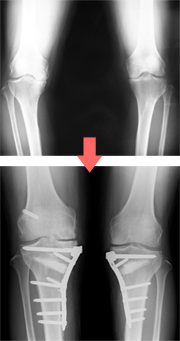

膝の場合には内側の軟骨がすり減りやすくO脚が進んでしまうので、脛骨というスネの骨を矯正することでO脚を直し、痛みを取る手術も行なっています。